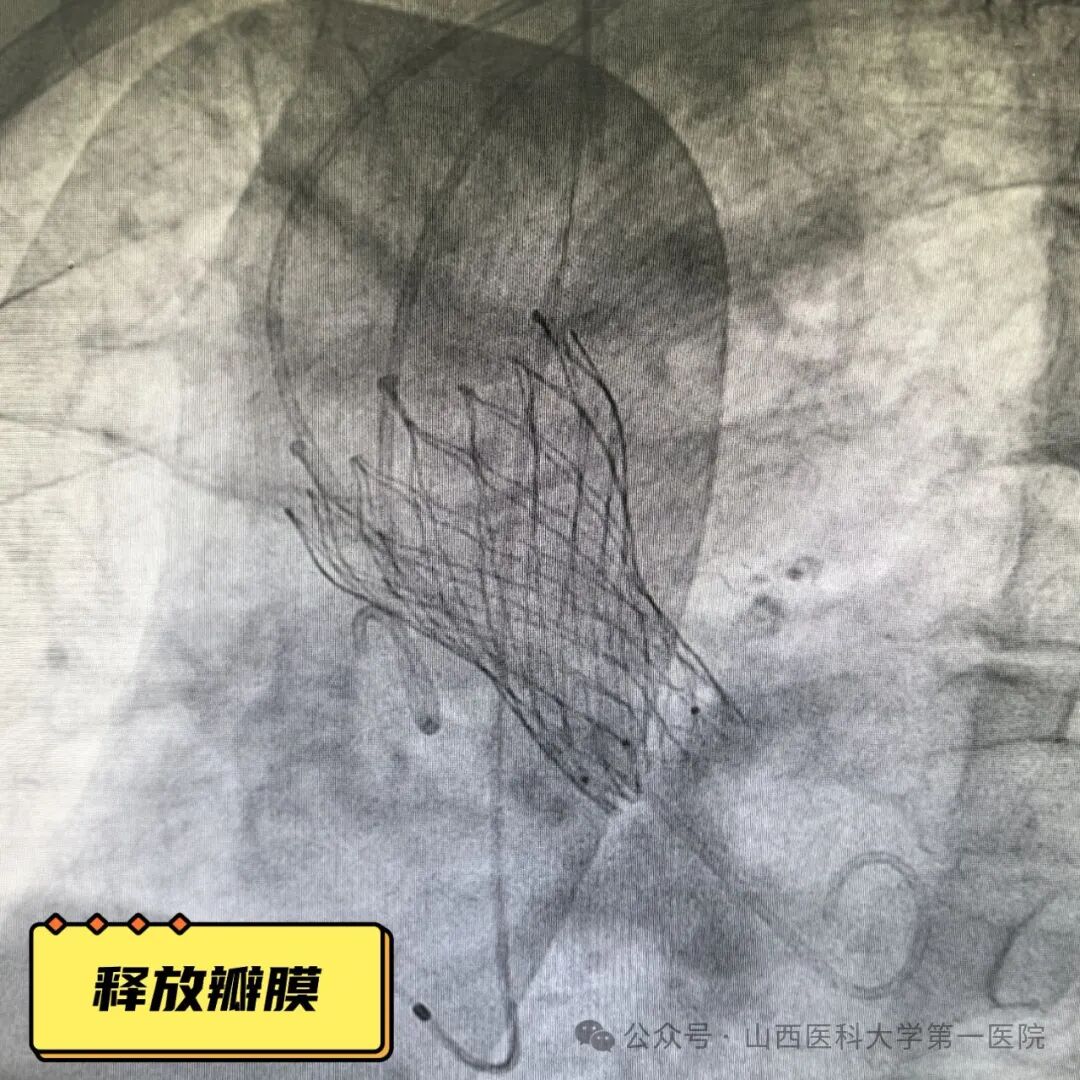

70岁的王大爷近三年来反复出现活动后心慌、气短,1个月前症状明显加重,出现1次晕厥,当地医院诊断为:主动脉瓣重度狭窄,建议手术治疗,为求进一步诊治来到山医大一院心脏大血管外科。患者既往有心梗病史,2016年曾于前降支植入一枚支架,郭建军主任医师、曹森垚副主任医师接诊后高度重视患者,入院后完善心脏彩超及化验指标提示:主动脉瓣重度狭窄,心功能不全,射血分数34%,NT-proBNP 3494pg/ml,积极调整心功能,同时综合考虑病情及年龄认为经导管主动脉瓣置换术(TAVR)是最佳手术方式,随后进一步完善TAVR术前检查,静息心肌灌注断层显像示:左室壁心尖段、前壁中间段和基底段薄弱,LVEF:30%,颈-胸CTA提示:主动脉瓣二叶畸形,重度钙化,心脏角度约66°。

经积极治疗及系统检查后,患者病情仍不容乐观,心功能极差,经反复抗心衰治疗效果不佳,围术期心功能衰竭风险高;主动脉瓣狭窄严重,瓣口面积小,瓣周钙化严重,钙化积分高,导丝跨瓣难度大,球囊扩张后斑块脱落致体循环栓塞风险高;横位心导致手术难度大、瓣架移位风险高;左室壁薄弱,术中出现心脏穿孔风险高;单纯主动脉瓣狭窄,术中循环崩溃可能大。郭建军主任医师团队格外慎重,为保证手术顺利进行多次组织心血管内科、神经内科、麻醉科、手术供应室、超声影像科及CT放射影像科等多学科会诊,经反复研究,针对术中可能出现的情况和并发症做了充分准备和相关预案,最终在结构性心脏病介入团队的默契配合及多学科医护人员的协助下,顺利完成TAVR手术。患者术后第二日便可下地活动,自觉症状明显好转,复查心脏彩超显示:主动脉瓣开放正常,跨瓣流速及压差正常,未见反流,心功能明显好转,LVEF54%。